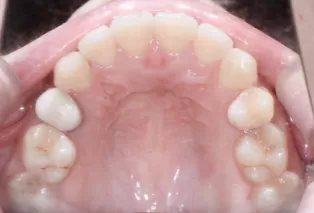

Intraoral photos after treatment